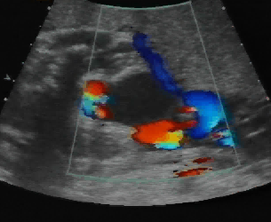

Above. Urachal cyst. Color Doppler demonstrates blood flow through the umbilical vessels but no blood flow to the cyst itself, which excludes the possibility of umbilical vein varix.